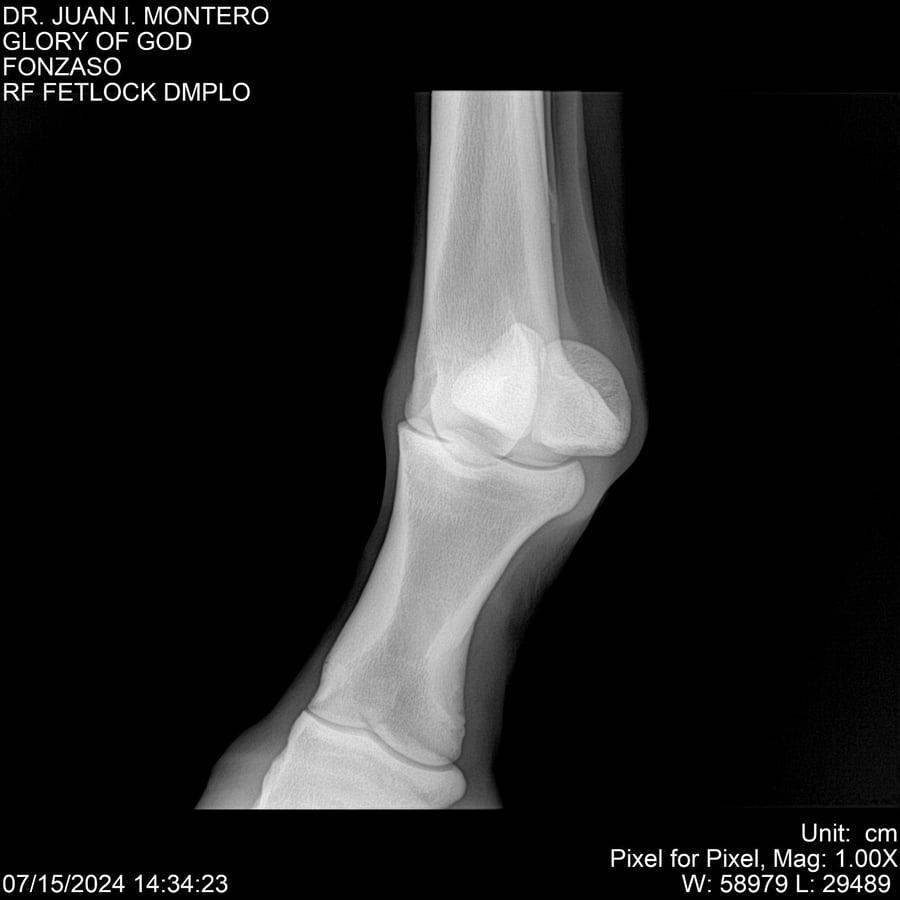

LOTE 10, GLORY OF GOD 🔥 🔥 🔥 Lote Anterior Volver al remate Lote Siguiente Ficha Contacto Montevideo - Ficha del Lote Identificador: #281389 Categoría: Yeguarizos Montevideo - 115 Visualizaciones ClicData Contacto Empresa: Abelenda N. R., Walter Hugo Nombre*: Teléfono* : E-mail* : Mensaje Enviar Registrese gratis Este contenido Exclusivo está disponible sólo para usuarios registrados Ingresar